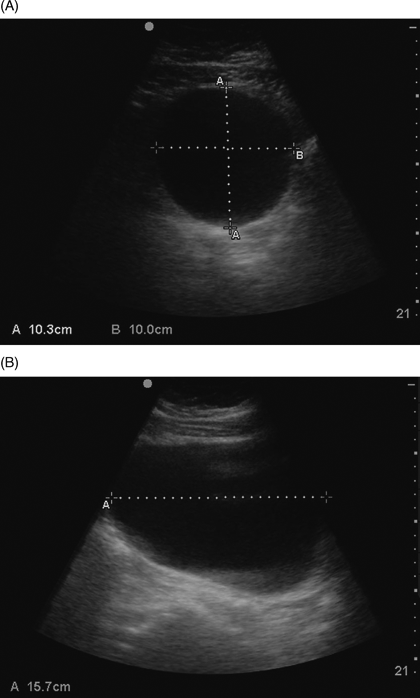

View Distended Bladder Ultrasound Images. Methods of ultrasound of the bladder. Ultrasound examinations are often done as part.

Ultrasound examinations are often done as part. Bladder outlet obstruction (or obstructive uropathy) occurs when urine is unable to flow from the kidneys through the ureters and out of the bladder through the urethra. Possible causes, signs and symptoms, standard treatment options and means of the transducer uses sound waves to make images of your bladder.

Partyially distended bladder at time of ultrasound just means you had some urine present, which is normal.